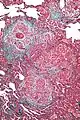

High magnification photomicrograph of a lung biopsy taken showing chronic hypersensitivity pneumonitis (H&E), showing mild thickening of the walls of the small air sacs by invasion of white blood cells. A multinucleated giant cell, seen within the walls of the air sacs to the right of the picture halfway down, is an important clue to the correct diagnosis.

Histopathology

Lung biopsy

Low magnification view of the histology of chronic hypersensitivity pneumonitis. The interstitium is expanded by a chronic inflammatory infiltrate. Two multinucleated giant cells can be seen within the interstitium at left, and a plug of organizing pneumonia at bottom left.

Lung biopsies can be diagnostic in cases of chronic hypersensitivity pneumonitis, or may help to suggest the diagnosis and trigger or intensify the search for an allergen. The main feature of chronic hypersensitivity pneumonitis on lung biopsies is expansion of the interstitium by lymphocytes accompanied by an occasional multinucleated giant cell or loose granuloma.[7][22]

When fibrosis develops in chronic hypersensitivity pneumonitis, the differential diagnosis in lung biopsies includes the idiopathic interstitial pneumonias.[23] This group of diseases includes usual interstitial pneumonia, non-specific interstitial pneumonia and cryptogenic organizing pneumonia, among others.[7][22]

The prognosis of some idiopathic interstitial pneumonias, e.g. idiopathic usual interstitial pneumonia (i.e. idiopathic pulmonary fibrosis), are very poor and the treatments of little help. This contrasts the prognosis (and treatment) for hypersensitivity pneumonitis, which is generally fairly good if the allergen is identified and exposures to it significantly reduced or eliminated. Thus, a lung biopsy, in some cases, may make a decisive difference.